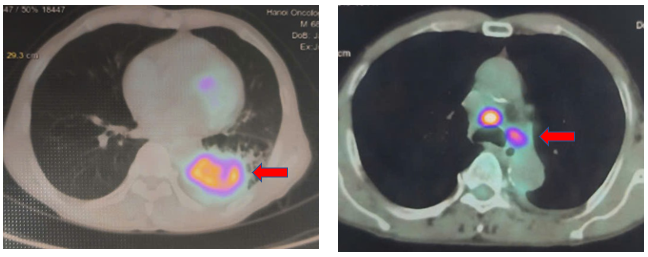

PET/CT: Khối mờ vùng rốn phổi trái kích thước 62x52x89 mm, thâm nhiễm bạch mạch, màng phổi, rãnh liên thùy, tăng chuyển hóa FDG SUVmax: 10,04. Nhiều hạch trung thất ở 2R, 4R, 5,6,7 hạch lớn nhất có đường kính 10mm tăng chuyển hóa FDG SUVmax: 11,49

Hình 3: Hình ảnh PET/CT: hình ảnh khối u phổi tăng chuyển hóa FDG SUVmax: 10,4 và hạch trung thất tăng chuyển hóa FDG SUVmax: 11,49, điển hình của tổn thương ác tính.